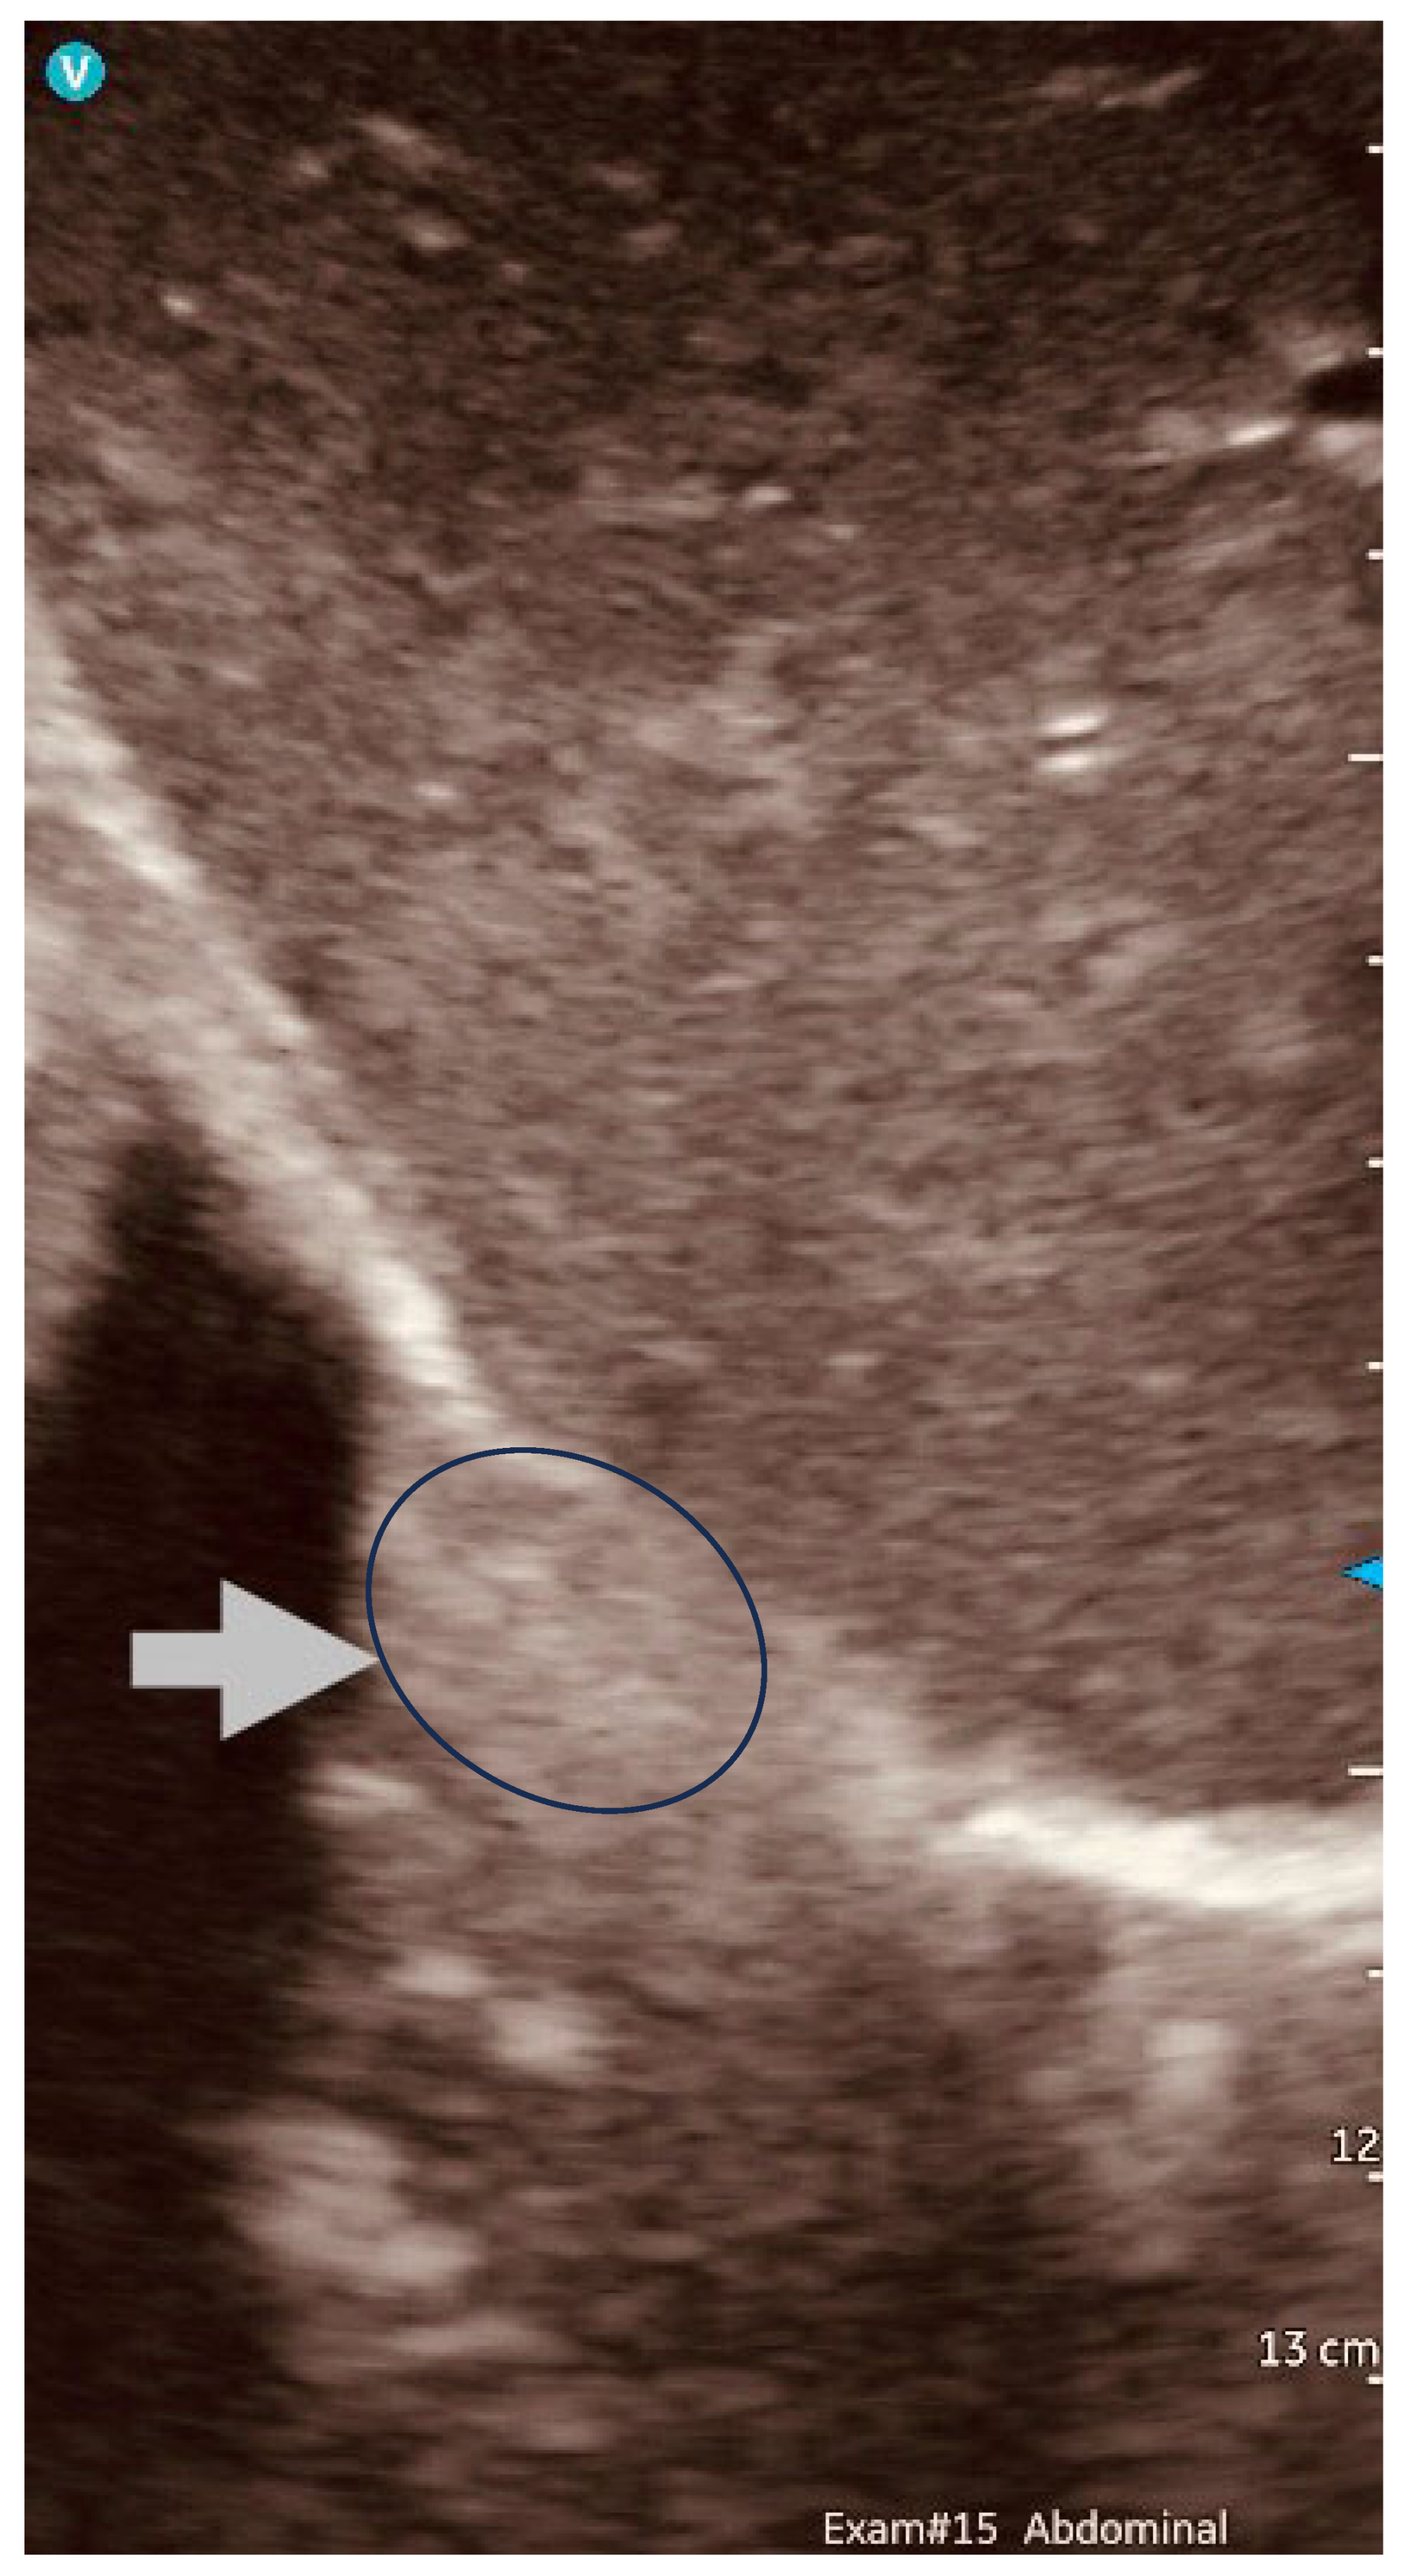

- IOUS in gynecological oncology lymph node assessment and staging

- Morphology (cortical thickening, spherical index, hilar integrity)

- Echostructure (heterogeneity, microcalcifications)

- Vascular dynamics (hilar vs. peripheral perfusion patterns)

- Biomechanical properties (strain elastography-derived stiffness ratios)

- Real-time confirmation of suspicious nodes before excision

- Precise needle guidance for targeted biopsy

- Immediate assessment of resection completeness

- Identification of critical vascular relationships to prevent injury